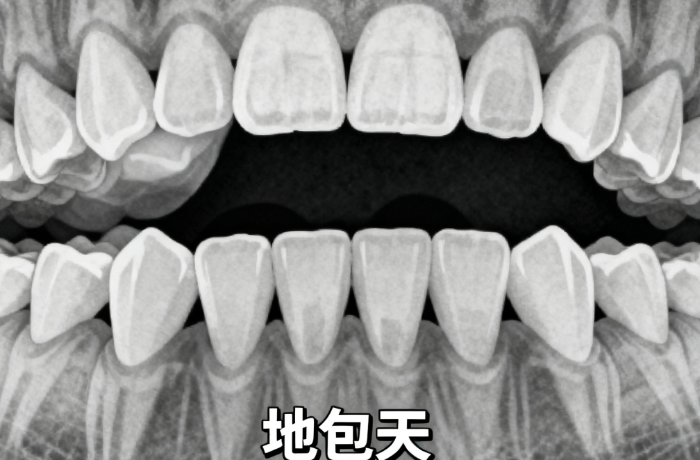

2、正畸項(xiàng)目價(jià)格親民

金屬托槽五千五起,適合學(xué)生黨或者預(yù)算有限的年輕人;隱形矯正時(shí)代天使一萬八千九起,隱適美三萬五起,雖然貴點(diǎn)但美觀度高,不影響社交。